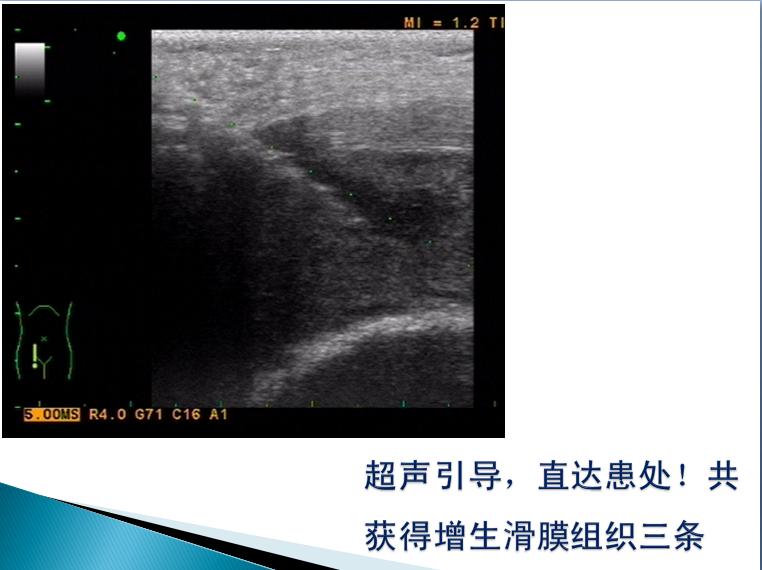

第三届中国超声造影大会病例大赛北医三院超声科获奖病例展示(四)